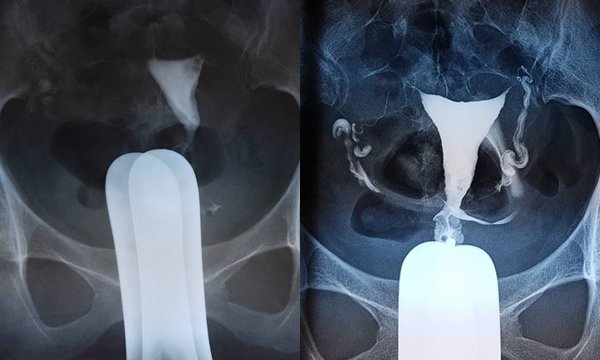

GS Nguyễn Viết Tiến – Thứ trưởng Bộ Y tế, Giám đốc Trung tâm Hỗ trợ sinh sản Quốc gia, “bàn tay vàng” vừa thực hiện thành công kỹ thuật này cho biết, đây là kỹ thuật nong vòi tử cung bằng catheter qua soi buồng tử cung kết hợp với nội soi ổ bụng là kỹ thuật hiện đại lần đầu tiên được áp dụng thành công tại Việt Nam.

Với phương pháp mới, bác sĩ sẽ nong vòi tử cung bằng catheter qua soi buồng tử cung kết hợp với nội soi ổ bụng. Đặc biệt, chi phí phẫu thuật chỉ ngang chi phí mổ nội soi, thời gian mổ ngắn: 30 phút đến 1 tiếng.

Với việc áp dụng kỹ thuật mới mỗi tuần tại trung tâm có thể làm cho hàng chục trường hợp. Kỹ thuật mới này là phẫu thuật có kiểm soát qua nội soi ổ bụng nên sẽ ít xảy ra những tai biến như thủng vòi tử cung, chảy máu, viêm phúc mạc sau nong.